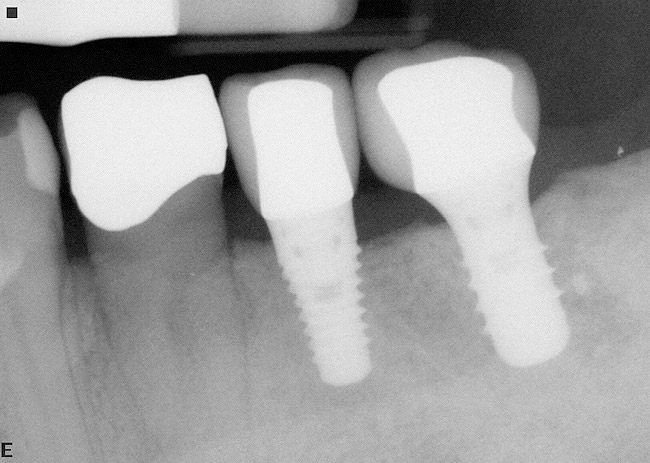

If the most crestal aspect of the interradicular bone is at least 3-mm-wide mesio-distally: A 2.2-mm-wide guide bur is drilled to the appropriate length, a guide pin is inserted, and a radiograph is taken (Figure 7). If necessary, the initial osteotomy is extended apically. A tapered osteotome is inserted into the osteotomy and moved mesio-distally and bucco-lingually to expand the osteotomy site. A 2.8-mm bur is used to prepare the osteotomy to depth, and a 2.8-mm-wide tapered osteotome is inserted in the osteotomy and once again utilized in mesio-distal and bucco-lingual directions to expand the osteotomy site. If the mesial and distal aspects of the interradicular bone are still intact at this point, a 3.5-mm bur is utilized to prepare the osteotomy to depth. A 3.5-mm-wide osteotome is inserted into the osteotomy and utilized in the manner already described. A decision is made as to whether to place a tapered implant with a 4.1-mm-wide base and a 6.5-mm-wide neck, or to use a 4.8-mm-wide bur and prepare the osteotomy to depth, in anticipation of placement of an implant with a 4.8-mm-wide parallel wall body and a 6.5-mm-wide platform. The chosen implant is inserted into the osteotomy (Figure 8), appropriate regenerative materials are placed, and the flaps are sutured. Following maturation of the regenerating hard tissues, the implant is ready for restoration (Figure 9). A radiograph taken 54 months after implant restoration demonstrates stability of the peri-implant crestal bone (Figure 10).

Case reports of these techniques can be seen in Figure 11 through Figure 19.